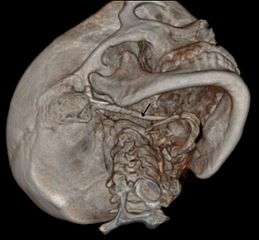

Imaging is important and is diagnostic. Visualizing the styloid process on a CT scan with 3D reconstruction is the suggested imaging technique.[6] The enlarged styloid may be visible on an orthopantogram or a lateral soft tissue X ray of the neck.